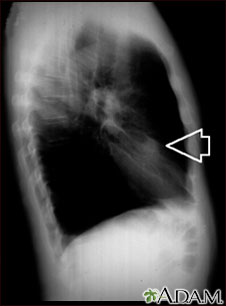

Nódulo pulmonar, lóbulo medio derecho- Radiografía de tórax

Esta es una radiografía de tórax (RXT) de un nódulo en el pulmón derecho.